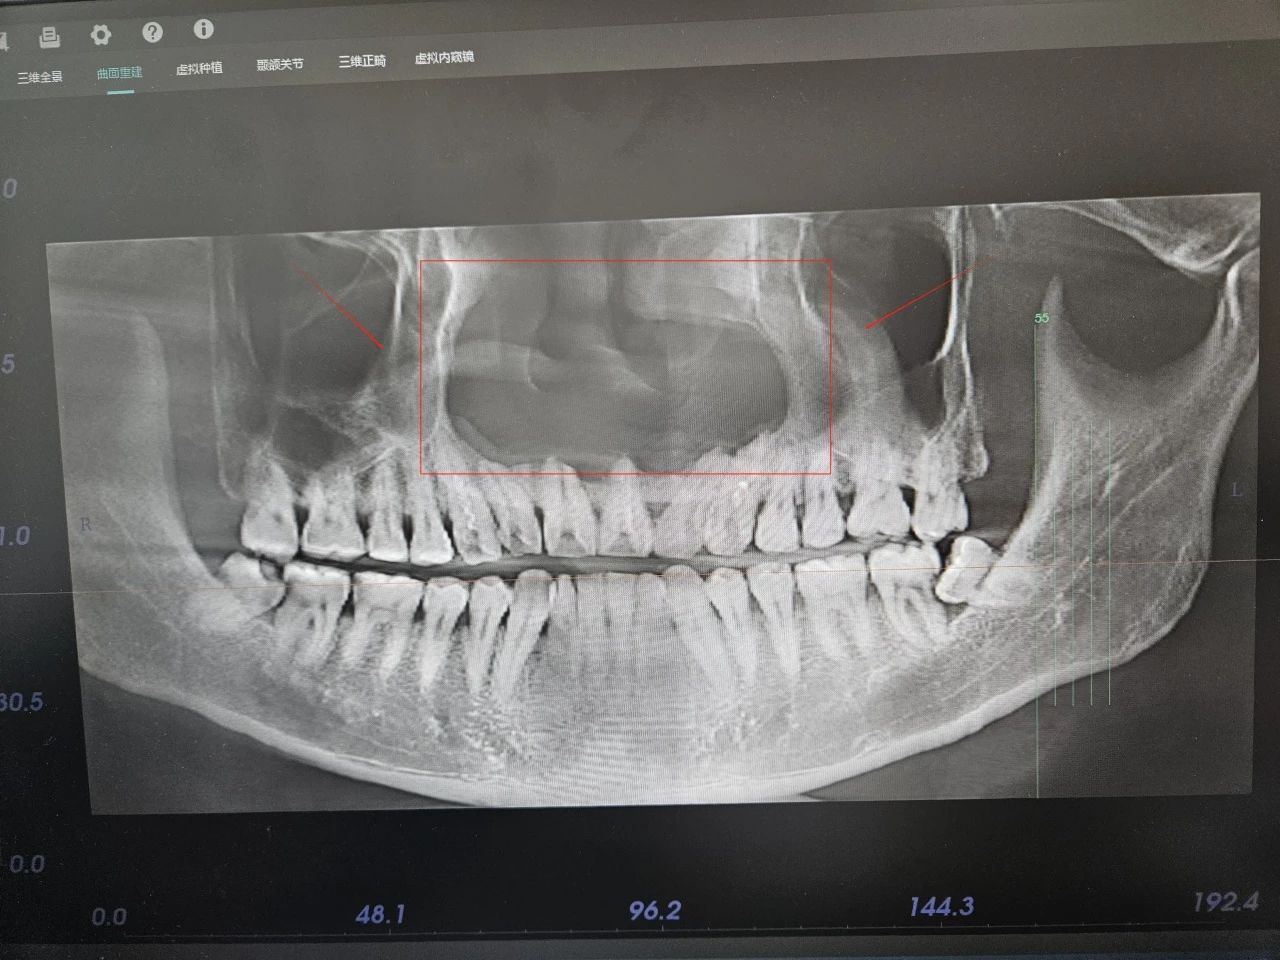

上颌骨5cm巨大囊肿,两侧上颌窦与鼻底相通!

口腔科黄利主任接诊后,经查体及结合影像报告发现,患者上颌骨的囊肿已经达到了惊人的4cm*5cm,而且两侧上颌窦和鼻底都已经相通,为防止囊肿进一步发展,导致上颌骨进一步破坏吸收,必须尽早进行手术治疗。

(术前CT影像)